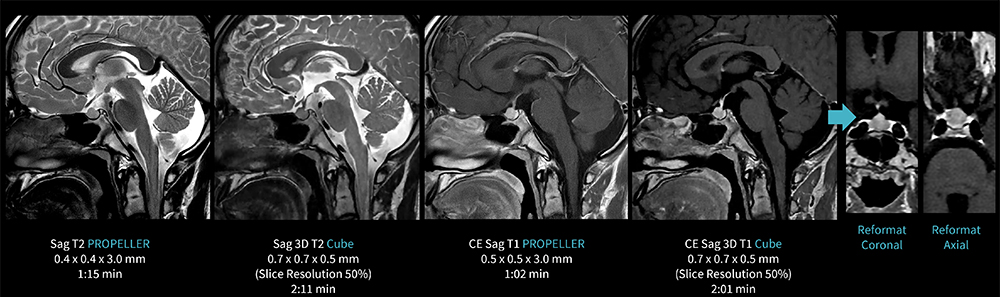

Case2 PROPELLER & Cube/中枢性思春期早発症による下垂体造影

10代、男性。中枢性思春期早発症にて結節疑いのため造影下垂体MRI検査を施行した。

血管からのフローアーチファクトを抑えるために2DはAIR Recon DLを併用したPROPELERを撮像した。

また、造影後においてThin sliceやReformatでの観察のため、AIR Recon DLを併用した3D Cubeも撮像している。

図2 PROPELLER とCubeを用いた下垂体造影検査